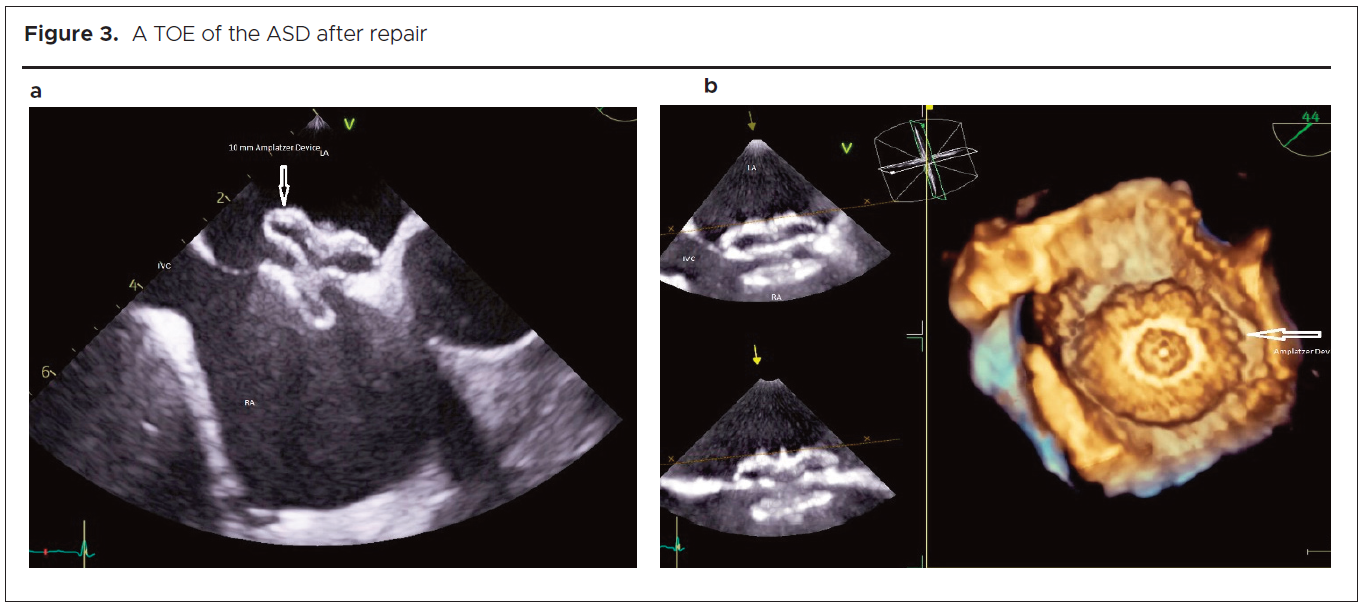

With limb-threatening ischaemia identified, bilateral iliac embolectomy and a kissing common aorto-iliac revascularisation procedure took place. Following recovery from this, in July 2024, she underwent successful ASD AmplatzerTM device closure (figures 3a and b).

A TOE showing a pulmonary-to-systemic flow ratio (Qp/Qs) of 1.6:1 is indicative of a significant left-to-right shunt. Along with paradoxical embolism, it was an indication for closure of the atrial communication in our patient.